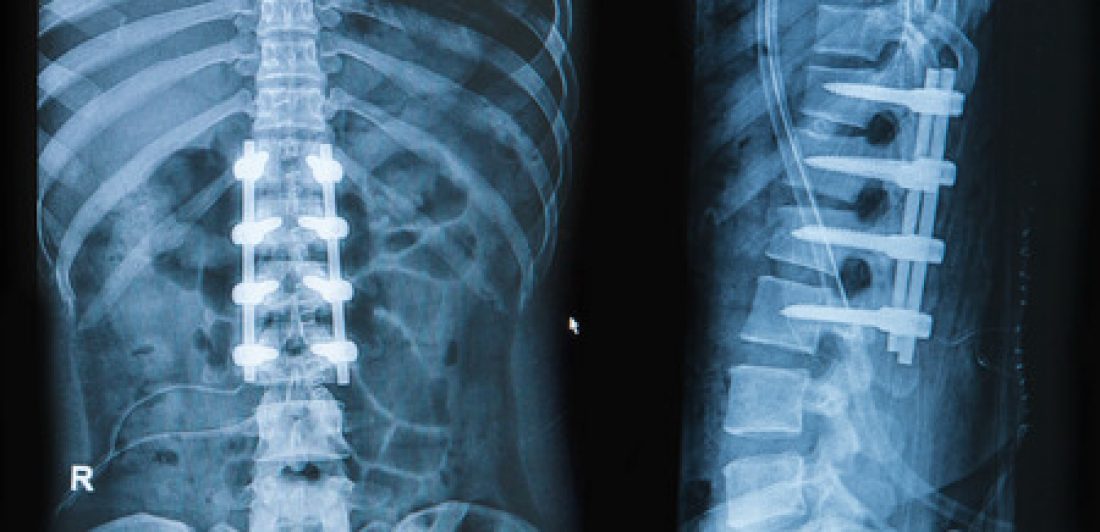

Durante una colisión, si el conductor chocó contra un objeto estacionario u otro vehículo chocó por detrás con el conductor, los ocupantes del vehículo experimentan una gran cantidad de fuerza durante un choque. La fuerza tiene el potencial de tensar los músculos, las articulaciones y los huesos y causar lesiones graves. Hay dos tipos de lesiones generadoras de dolor en la columna vertebral que son bastante comunes en choques automovilísticos, lesiones de disco y lesiones en las articulaciones cigapofisarias.

Lesiones discogénicas: el dolor asociado con los discos espinales se llama dolor discogénico. Los discos espinales son piezas redondas de cartílago que actúan como un amortiguador entre cada hueso. Este cartílago forma la columna vertebral y permite movimiento y estabilidad. El daño a uno o más de los discos espinales puede provocar dolor intenso durante toda la vida.

Lesiones en las articulaciones cigapofisarias: Estas articulaciones son lo que permite que la columna se mueva con facilidad y soporte nuestro peso. Rodeado por una membrana flexible, las articulaciones cigapofisarias secretan un líquido para lubricar las articulaciones para facilitar el movimiento entre cada vértebra. Además, las articulaciones cigapofisarias y los discos espinales trabajan en conjunto para permitir un movimiento controlado en todo el cuerpo. Una persona con una lesión en las articulaciones cigapofisarias experimentará dolor lumbar que puede extenderse a las nalgas y las piernas.